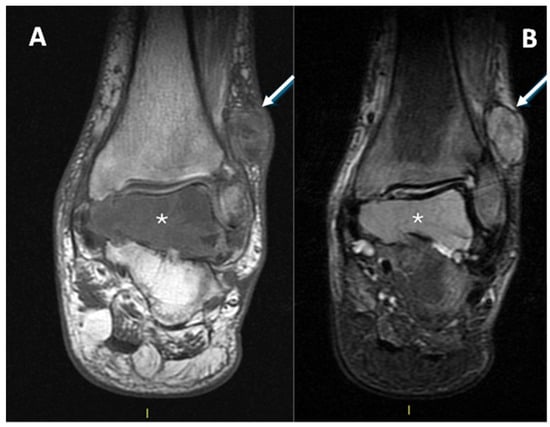

1.1. General Characteristics, History and Epidemiology

1.3. Imaging and Clinical Features

1.3.2. Magnetic Resonance Imaging

3.4. MRI Features

3.4.1. General MRI Features

3.4.2. Peritumoral Edema

3.4.3. Other MRI Features